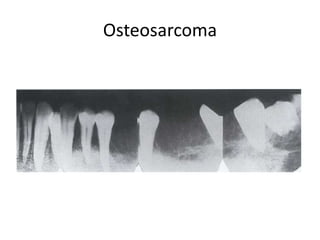

Osteosarcoma

Effects on surrounding structures:

i-Early :widening of the

periodontal membrane

• Loss of cortices and lamina dura.

• Floating or hanging teeth

ii-Late :

• poorly defined osteolytic,

osteoblastic

• mixed pattern of

“Sunray” Periosteal Reaction

• Osteosarcoma